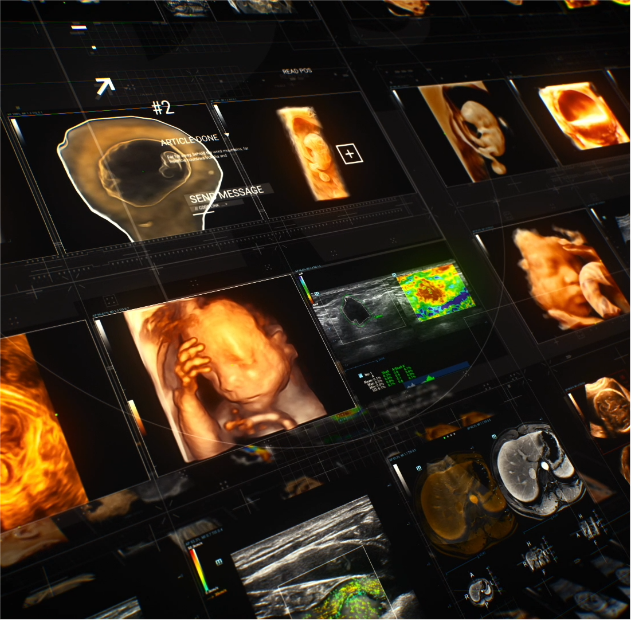

![continuous-use-germany-largest-ultrasound-department-mindray-resona-family.thumb.1280.1280 Im Dauereinsatz in Deutschlands gr??ter Ultraschall-Abteilung ŌĆō die Resona-Familie von Mindray]() Customer Stories | Allgemeine BildgebungIm Dauereinsatz in Deutschlands gr??ter Ultraschall-Abteilung ŌĆō die Resona-Familie von Mindray

Customer Stories | Allgemeine BildgebungIm Dauereinsatz in Deutschlands gr??ter Ultraschall-Abteilung ŌĆō die Resona-Familie von Mindray -

![resona-i9-pediatric-ultrasound-landshut.thumb.1280.1280 Alles unter Dach und Fach - Kinderkrankenhaus St. Marien in Landshut schafft drei neue Ultraschallger?te Resona I9 an]() Customer Stories | Point-of-care ultrasoundAlles unter Dach und Fach - Kinderkrankenhaus St. Marien in Landshut schafft drei neue Ultraschallger?te Resona I9 an

Customer Stories | Point-of-care ultrasoundAlles unter Dach und Fach - Kinderkrankenhaus St. Marien in Landshut schafft drei neue Ultraschallger?te Resona I9 an -

![ultrasound-tech-supports-mol-hospital-heart-failure-study.thumb.1280.1280 Mindray Ultraschalltechnologie unterst├╝tzt das Krankenhaus MOL bei einer Studie zur verbesserten Behandlung von Herzschw?che]() Ultraschall | Customer StoriesMindray Ultraschalltechnologie unterst├╝tzt das Krankenhaus MOL bei einer Studie zur verbesserten Behandlung von Herzschw?che

Ultraschall | Customer StoriesMindray Ultraschalltechnologie unterst├╝tzt das Krankenhaus MOL bei einer Studie zur verbesserten Behandlung von Herzschw?che -

![switch-off-pain-ultrasound-controlled-trunk-blocks.thumb.1280.1280 Schmerz abschalten mit ultraschallgesteuerten Rumpfblockaden]() Ultraschall | An?sthesieSchmerz abschalten mit ultraschallgesteuerten Rumpfblockaden

Ultraschall | An?sthesieSchmerz abschalten mit ultraschallgesteuerten Rumpfblockaden -

![sharp-accurate-ultrasound-guided-regional-anesthesia-te7.thumb.1280.1280 Gestochen scharf ans Ziel: Ultraschallgest├╝tzte Regionalan?sthesie mit dem TE7]() An?sthesie | UltraschallGestochen scharf ans Ziel: Ultraschallgest├╝tzte Regionalan?sthesie mit dem TE7

An?sthesie | UltraschallGestochen scharf ans Ziel: Ultraschallgest├╝tzte Regionalan?sthesie mit dem TE7 -

![dhaifalah-and-fetmed-clinic-elevating-women-healthcare-in-czech.thumb.1280.1280 Dr. Dhaifalah und die FETMED-Klinik: Verbesserung der Gesundheitsversorgung von Frauen in der Tschechischen Republik]() Customer Stories | GH GYNDr. Dhaifalah und die FETMED-Klinik: Verbesserung der Gesundheitsversorgung von Frauen in der Tschechischen Republik

Customer Stories | GH GYNDr. Dhaifalah und die FETMED-Klinik: Verbesserung der Gesundheitsversorgung von Frauen in der Tschechischen Republik -

![innocent-smile-sjd-barcelona-childrens-hospital.thumb.1280.1280 F├╝r mehr gl├╝ckliche Kindergesichter]() Interconnectivity | Optimal workflowF├╝r mehr gl├╝ckliche Kindergesichter

Interconnectivity | Optimal workflowF├╝r mehr gl├╝ckliche Kindergesichter -

![what-if-you-could-have-gps-for-ultrasound-guided-procedure.thumb.1280.1280 Was w?re, wenn Sie GPS f├╝r ultraschallgef├╝hrte Verfahren h?tten?]() Ultraschall | Intelligente AnwendungenWas w?re, wenn Sie GPS f├╝r ultraschallgef├╝hrte Verfahren h?tten?

Ultraschall | Intelligente AnwendungenWas w?re, wenn Sie GPS f├╝r ultraschallgef├╝hrte Verfahren h?tten?